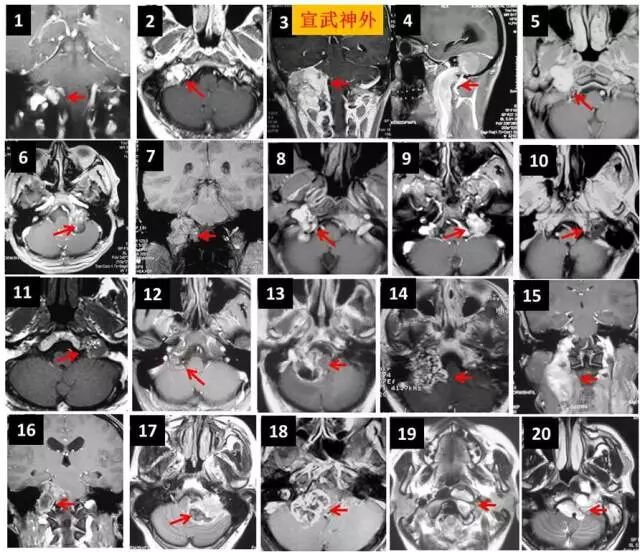

颅底疾病全覆盖

手术体位及入路

听神经瘤

手术体位个性化选择

嗅沟脑膜瘤

岩斜脑膜瘤

脑桥海绵状血管瘤

颈静脉孔区肿瘤

颈静脉孔内外沟通型神经鞘瘤

内镜经口+乙状窦后入路显微手术 分期手术

幕上下联合入路

颈静脉球瘤

内镜经鼻蝶切除垂体瘤

内镜经鼻蝶切除颅咽管瘤

微血管减压术